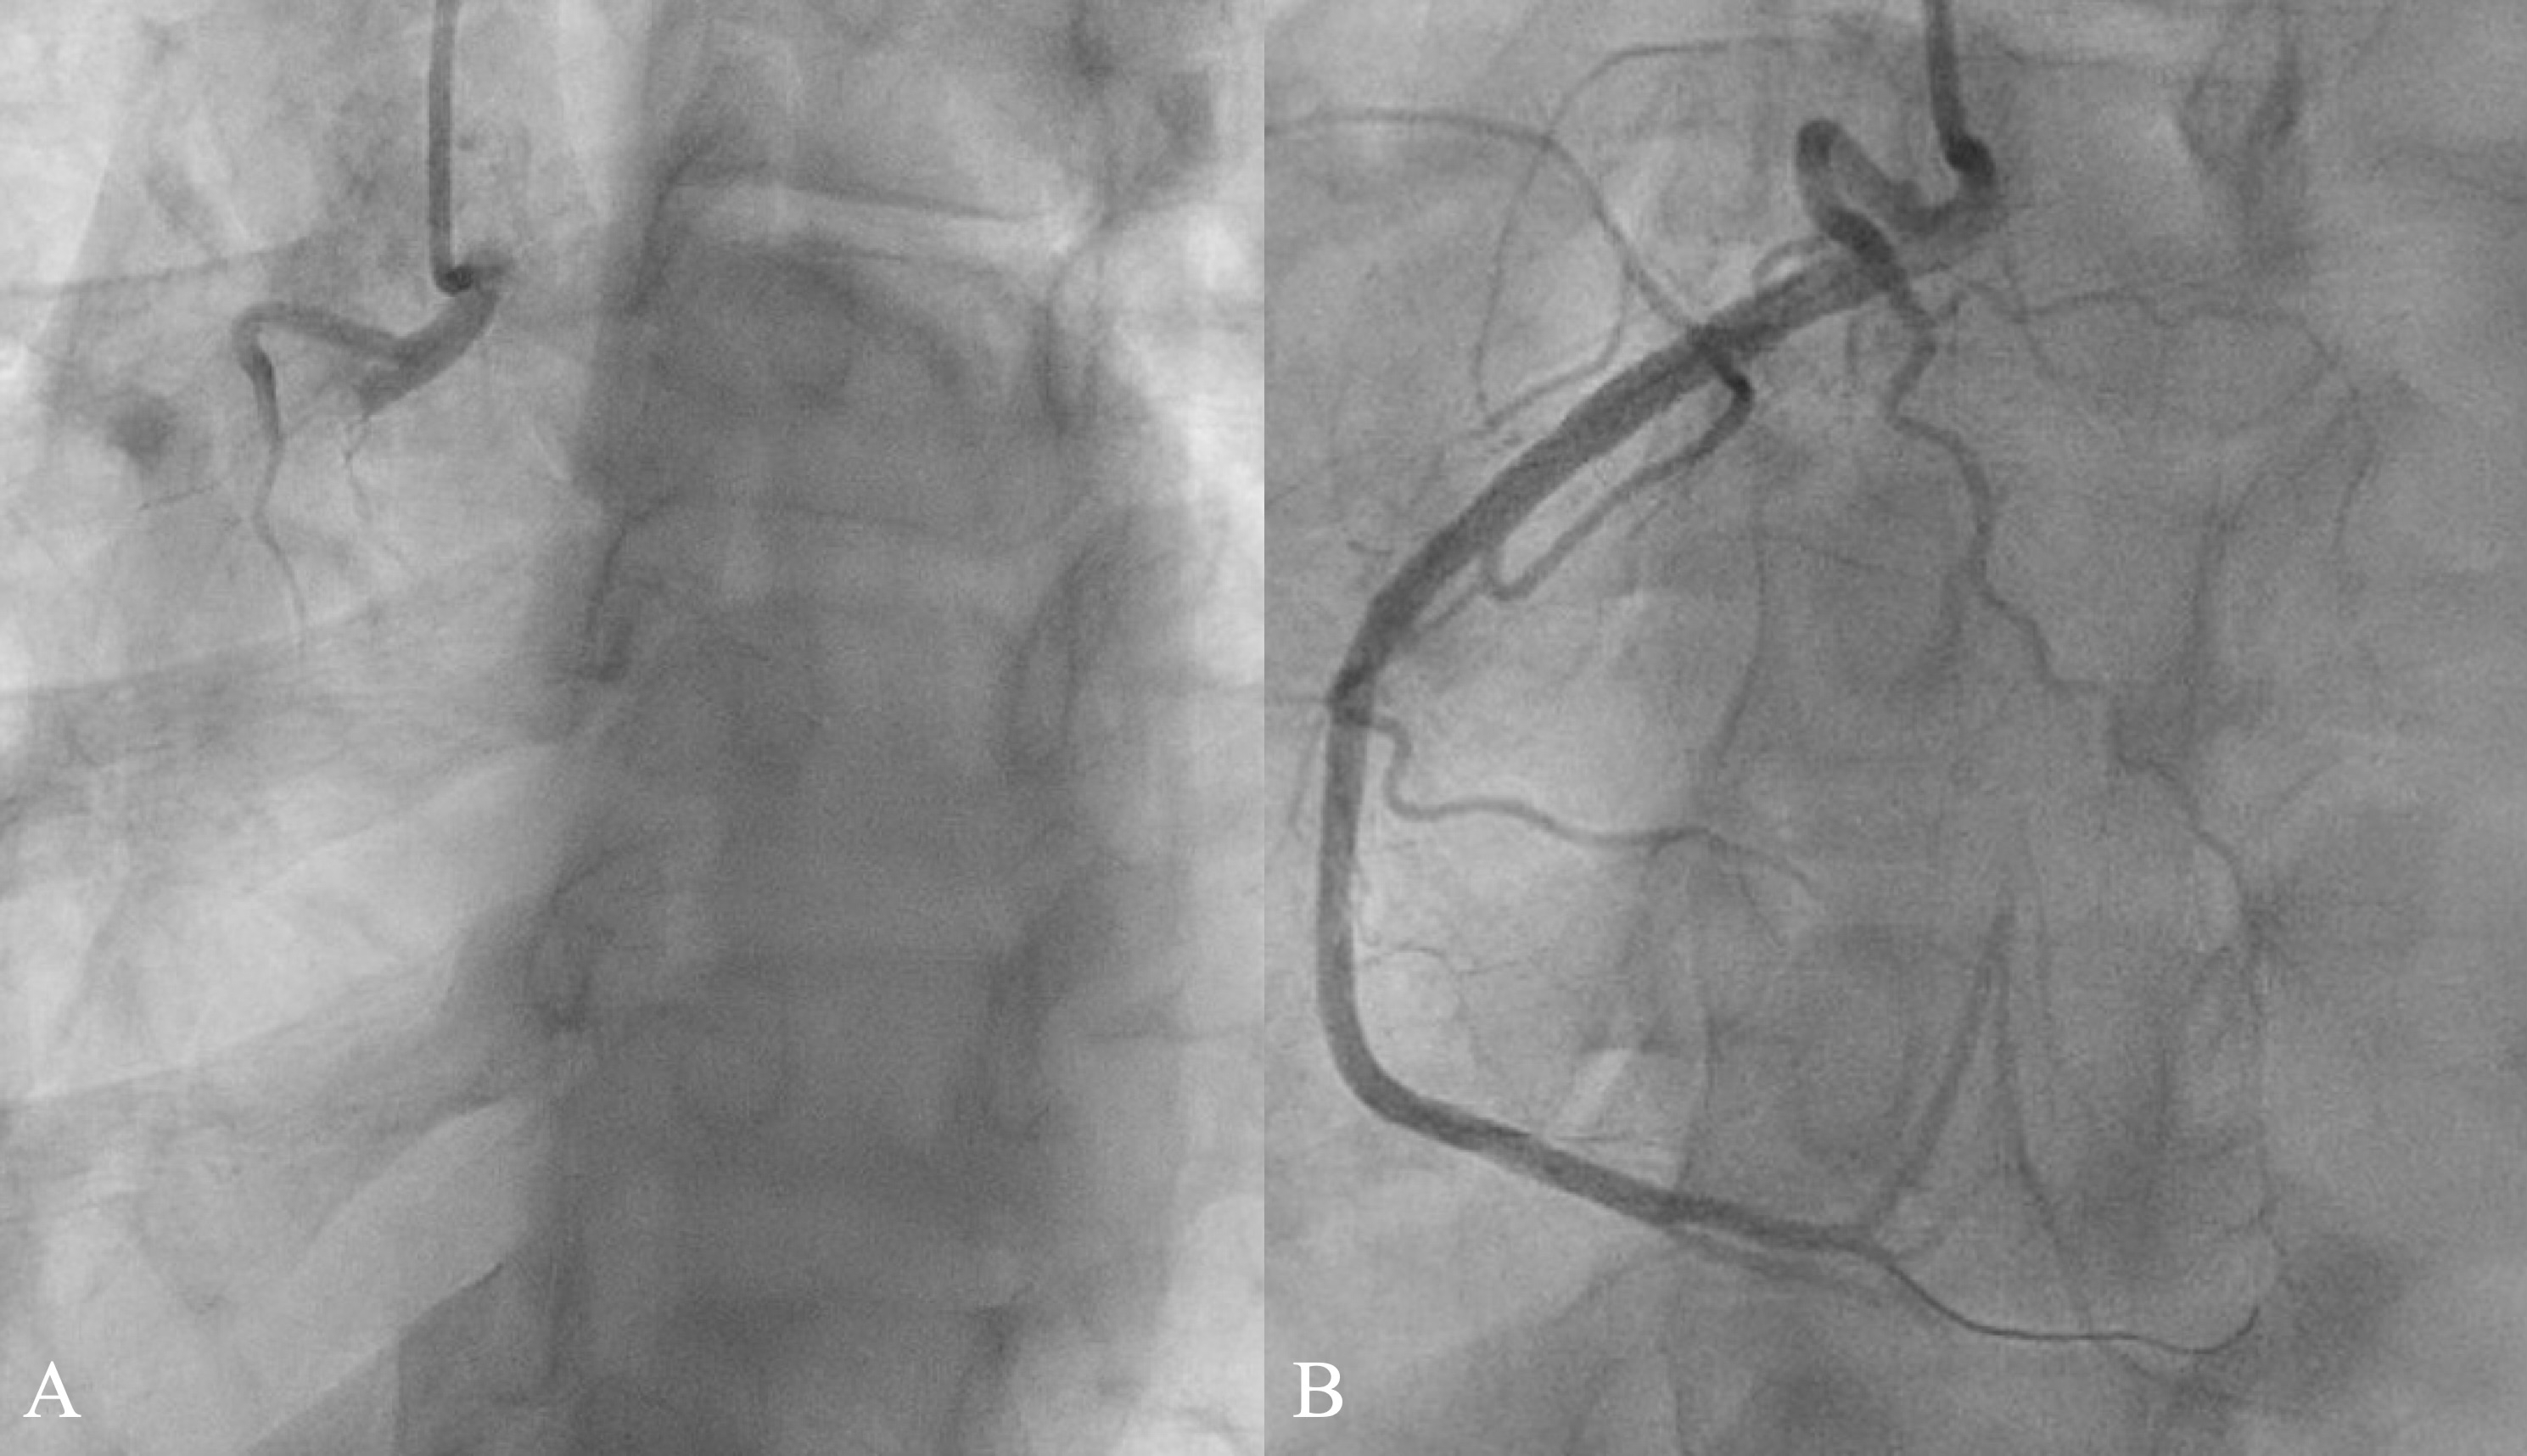

Occlusion myocardial infarctions (OMI) can present with minimal ECG changes, making diagnosis challenging without high clinical suspicion. STEMI criteria have limited sensitivity for acute coronary occlusion (ACO), and patients with NSTEMI with ACO have longer time to angiography and worse outcomes compared to patients with STEMI and ACO. We present a 43-year-old male with BMI 36, hypertension, and a 30 pack-year smoking history presented with three days of intermittent chest pain radiating to the back with nausea and dyspnea. Symptoms progressed, prompting repeated visits to urgent care and ultimately to the emergency department (ED). On ED arrival, ECG was non-diagnostic. Troponin I was markedly elevated at 5,548 ng/L. Serial ECG revealed hyperacute T waves without conventionally diagnostic ST elevation and troponin rising to 25,763 ng/L. The patient underwent coronary angiography 13 hours after arrival, revealing acute thrombotic occlusion of the proximal right coronary artery. Percutaneous coronary internvention was performed with resolution of pain. Repeat ECG showed reperfusion changes, and echocardiogram showed inferior hypokinesis.